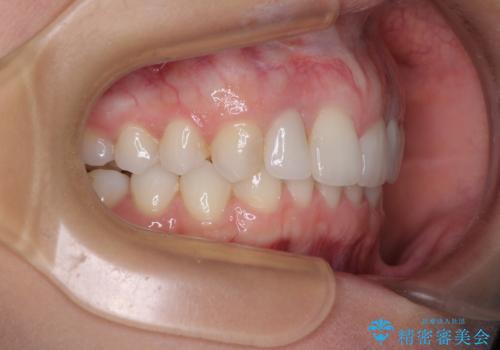

- 前歯の歯並びと神経を取って変色してしまった前歯を気にして来院された患者様です。

上下前歯の歯列不正はインビザラインにより整え、その後に、前歯2本をオールセラミッククラウンにて補綴治療することとしました。

下顎前歯が1本欠損しており、下顎歯列の大きさが本来よりも小さいため、上顎歯列とのバランスが悪く、深い咬み合わせになっていました。

上顎にIPRを多用して歯列の大きさを小さくするよう試みましたが、理想的な咬み合わせまでには改善させることはできませんでした。